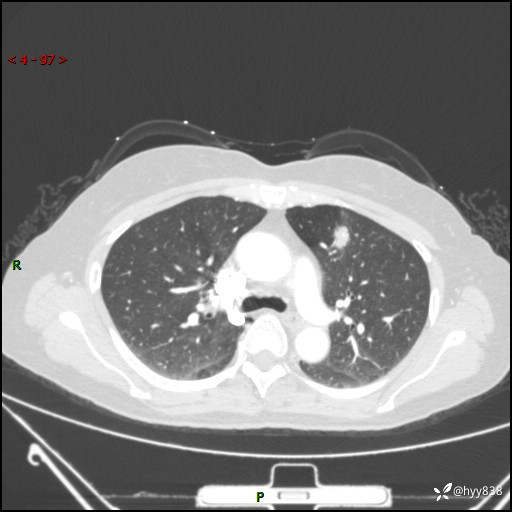

54岁/女,发现肺占位1天。观其形态和强化,术前我信心十足,术后我---结果公布~

【患者信息】:54岁/女

【主诉】:发现肺占位1天

【现病史及既往史】:患者2023.10.23体检发现肺占位:,2023.10.23当地区中心卫生院胸腹部CT:1.左肺上叶结节,考虑为占位可能;2.肝脏小囊肿灶;3.子宫左侧附件区畸胎瘤;无咳嗽咳痰,无恶心呕吐,无发热,无胸闷胸痛等不适;现患者为求进一步诊治来我院,门诊以“肺占位”收入我科。 患者自起病以来,精神饮食睡眠一般,大小便正常,体力体重无明显下降。

【检查】:胸部CT增强(外院平扫)